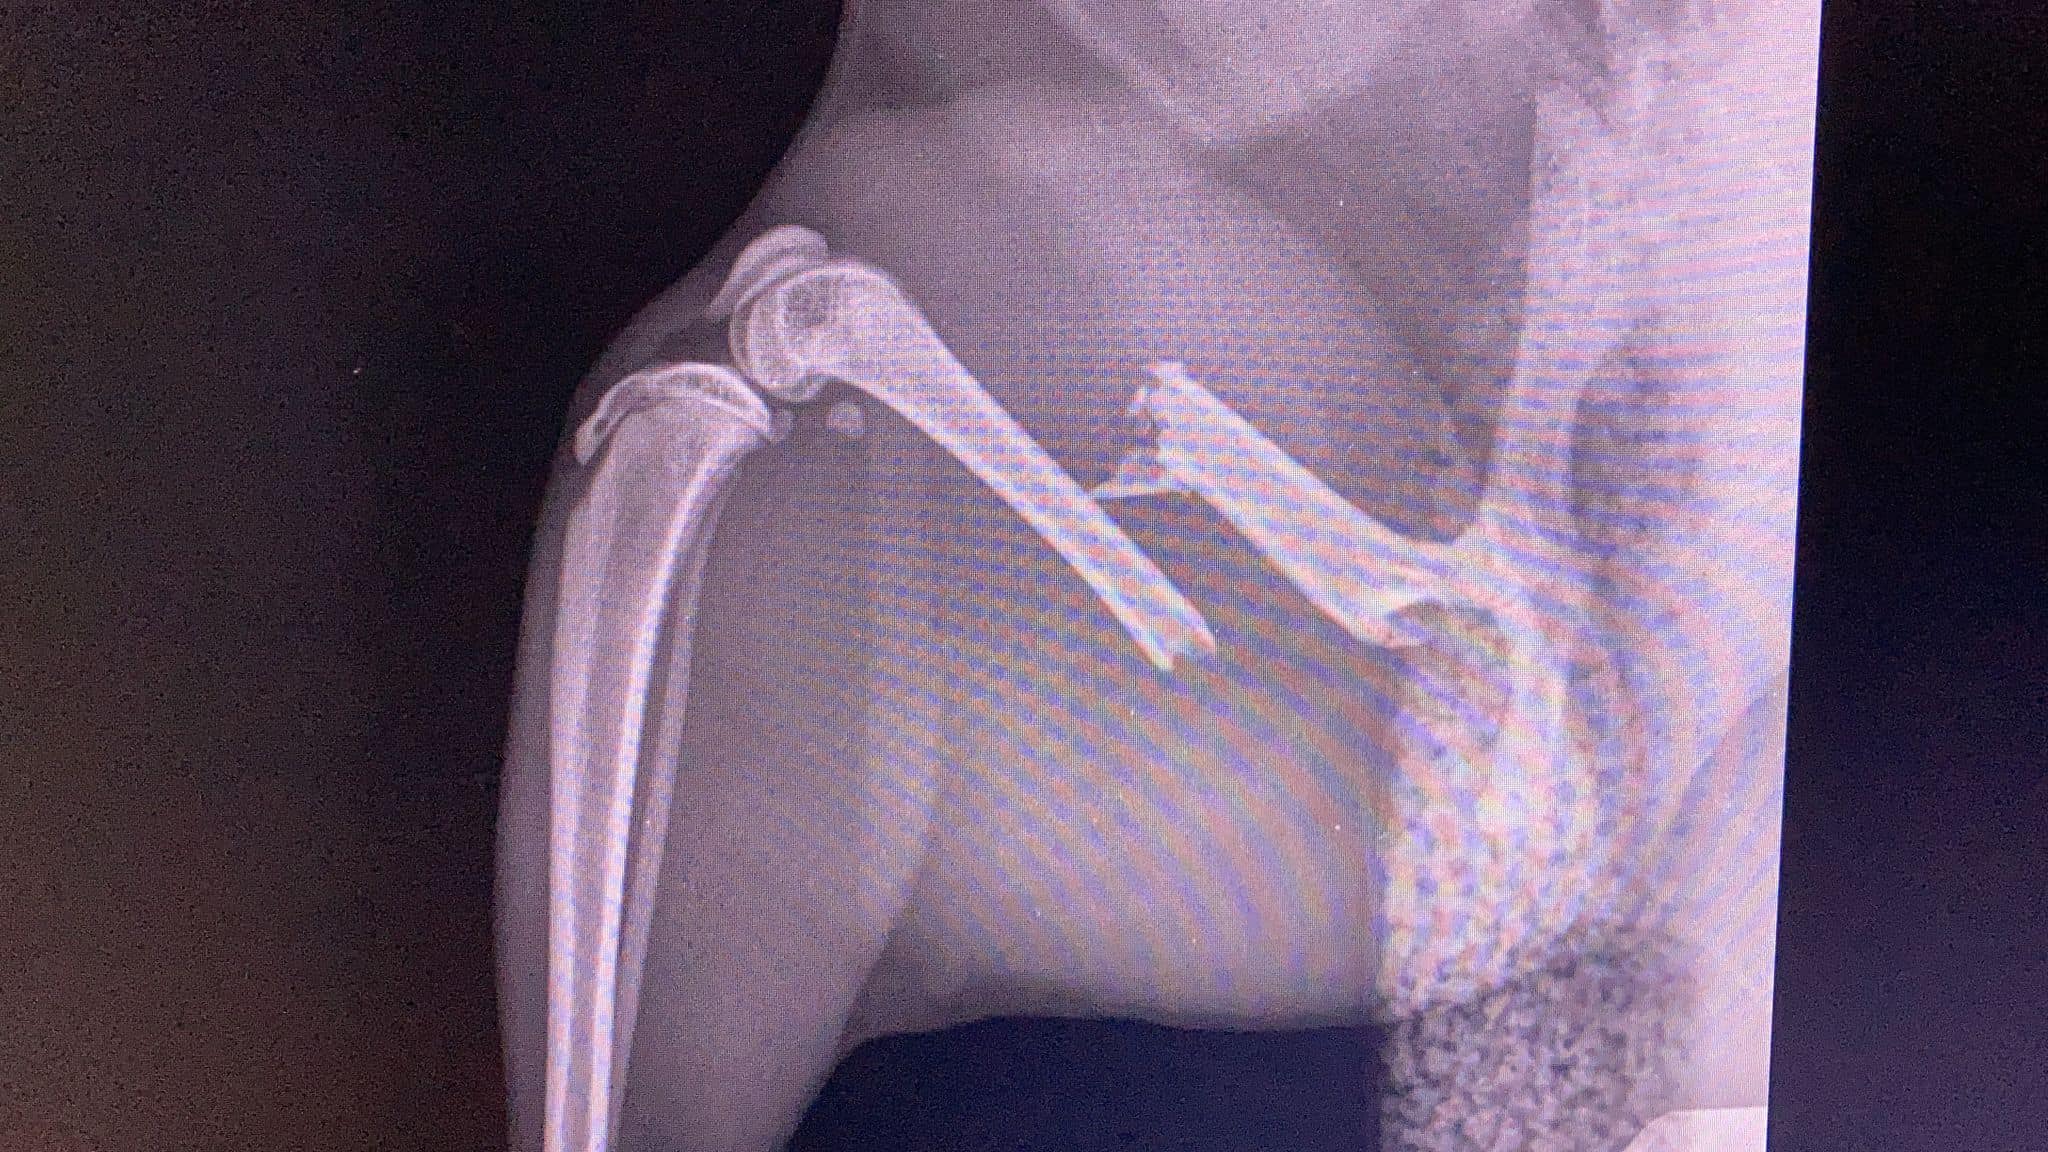

Selecting the appropriate fixation method in cats depends on fracture location and pattern, the cat’s overall health, and the sur...

Femoral fractures in cats are challenging injuries that require careful planning. Successful management balances mechanical stability with biological...

Feline femoral fractures are among the most challenging orthopedic injuries in small animal practices. Successful management demands an understanding...

Quadriceps contracture is a challenging but preventable complication in feline orthopaedic practice. It typically develops after femoral fra...